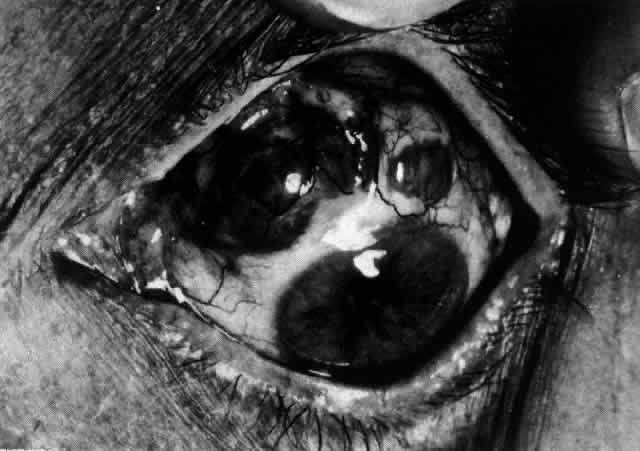

episcleritis and nodular episcleritis. ETIOLOGY Thirty percent of patients with episcleritis had some associated general conditions,6–8 but the rest defied all attempts to discover an etiology. Although some patients had a strong family history of atopy, results of patch and prick testing were uniformly negative. Of those in whom an etiology was found, only 5% showed any association with collagen disease, 7% had an association with herpes zoster, and 3% each had an association with gout or syphilis; the rest had associated conditions such as erythema nodosum, Schönlein-Henoch purpura, erythema multiforme, contact with industrial solvents, or penicillin sensitivity, indicating an immune basis for the condition. PATHOLOGY Microscopic and electron microscopic studies of biopsy specimens from patients with simple and nodular episcleritis have been totally noncontributory in the attempt to discover the etiology of this condition. The inflamed area is packed with lymphocytes and a few other inflammatory cells, but there are no mast cells, plasma cells, or eosinophils. CLINICAL MANIFESTATIONS The onset is usually acute; the eye may become red and painful in as short a time as half an hour. The patient's main complaint is redness of the eye, which is often sectorial and may be accompanied by a feeling of hotness, pricking, and mild discomfort. There is no discharge, although the eye waters occasionally. Pain may be absent, but the discomfort may be so severe that patients cannot pursue their normal occupation. The pain is localized to the eye, rarely radiating to the forehead and never producing the severe boring pain that is so commonly described in scleritis. In a severe attack the lids may become swollen, but this is a rare occurrence. If photophobia is present, an accompanying corneal condition should be suspected. Simple and nodular episcleritis differ in their clinical courses, but in both the edema and infiltration are entirely within the episcleral tissues. The sclera is not involved. The maximum congestion is in the superficial episcleral network, with some slight congestion of the conjunctival vessels and deep episcleral vessels (Fig. 10). The intraocular structures are not involved in either variety, nor is the visual acuity affected. Anterior segment fluorescein angiography reveals a normal vascular pattern but a very rapid flow rate, with the whole transit of the dye being completed within 2 or 3 seconds (Figs. 11 and 12).

The redness of simple episcleritis may be intense, varying from a fiery-red or a brick-red discoloration to a mild red flush, but it does not have the bluish tinge that is seen in scleritis. The distribution is usually sectorial but can involve the whole anterior segment of the globe. The episcleral vessels are engorged but retain their normal radial position and architecture (Figs. 13 and 14; Color Plate 1A). In simple episcleritis, there is a diffuse edema of the episcleral tissues. These tissues are sometimes infiltrated with gray deposits that appear yellow in red-free light. Surprisingly, the eye is rarely tender to the touch.